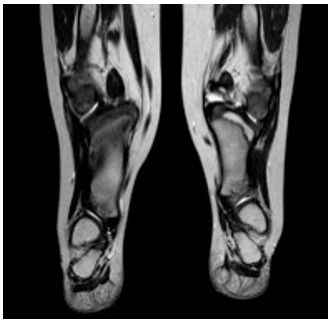

El tercer caso fue evidenciado en un paciente de 4 años de edad con hemimelia de la tibia, dado por hipoplasia bilateral de la tibia. Asociado, presentaba polidactilia, un compartimento posterior deficiente con pie equino-varo (figura 4).

Compartimento anterior deficiente y ausencia de ligamentos colaterales